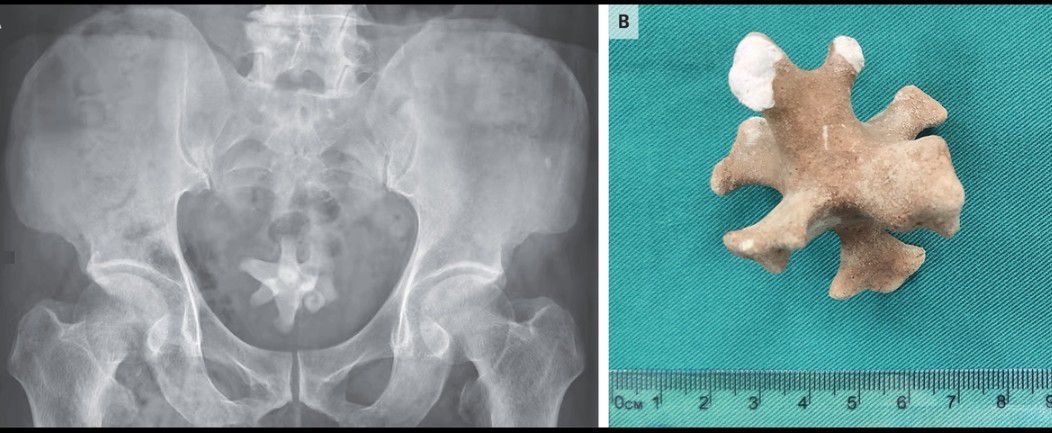

A 70-year-old man was referred to the urology clinic with a 3-month history of worsening symptoms in the lower urinary tract and new-onset hematuria. He had a history of recurrent urinary tract infections and benign prostatic hyperplasia, for which he had previously declined medications. However, 3 months earlier, he had started tamsulosin and finasteride to treat progressive dysuria, nocturia, frequency, and urgency. On physical examination, there was tenderness to palpation over the suprapubic region and an enlarged prostate. Urinalysis showed pyuria, hematuria, and bacteriuria. A urine culture grew extended-spectrum beta-lactamase–producing Escherichia coli, which was treated with ertapenem. Ultrasonography of the kidneys and bladder showed a small diverticulum in the posterior bladder wall and a large echogenic focus, indicating a possible bladder stone. A subsequent abdominal radiograph showed a large, irregularly shaped, radiopaque stone in the pelvis (Panel A). Transurethral enucleation of the prostate was performed, and a jackstone calculus measuring 5 cm in the largest dimension (Panel B) was removed from the bladder. Jackstone calculi — named after a toy jack — typically form in the bladder because of urine stasis and are composed of calcium oxalate dihydrate. At the 1-month follow-up, the patient’s symptoms had abated.